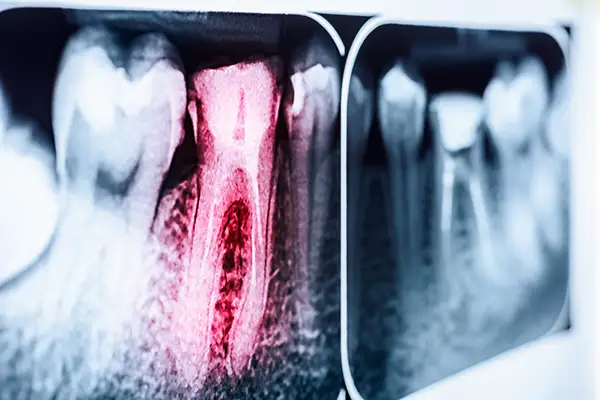

Dental X-ray highlighting an infected tooth root canal with inflammation in red.Endodontic Retreatment is designed for teeth that have had a previous root canal but are still causing problems. Retreatment reopens the tooth, removes the prior filling material, identifies what prevented healing, and reseals the canals using the latest techniques and materials.